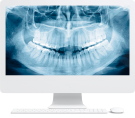

Этап 2

Ортопантомограмма + фотопротокол

Для выявления объема костной ткани в области отсутствующих зубов